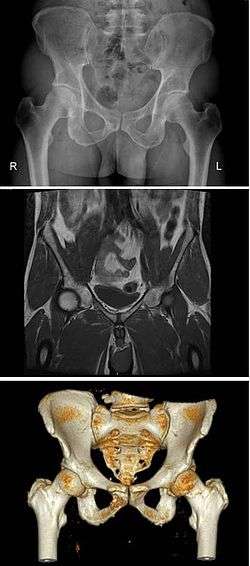

The pelvis (plural pelves or pelvises) is either the lower part of the trunk of the human body[1] between the abdomen and the thighs (sometimes also called pelvic region of the trunk) or the skeleton embedded in it[2] (sometimes also called bony pelvis, or pelvic skeleton).

The pelvic region of the trunk includes the bony pelvis, the pelvic cavity (the space enclosed by the bony pelvis), the pelvic floor, below the pelvic cavity, and the perineum, below the pelvic floor.[1] The pelvic skeleton is formed in the area of the back, by the sacrum and the coccyx and anteriorly and to the left and right sides, by a pair of hip bones. The two hip bones connect the spine with the lower limbs. They are attached to the sacrum posteriorly, connected to each other anteriorly, and joined with the two femurs at the hip joints. The gap enclosed by the bony pelvis, called the pelvic cavity, is the section of the body underneath the abdomen and mainly consists of the reproductive organs (sex organs) and the rectum, while the pelvic floor at the base of the cavity assists in supporting the organs of the abdomen.